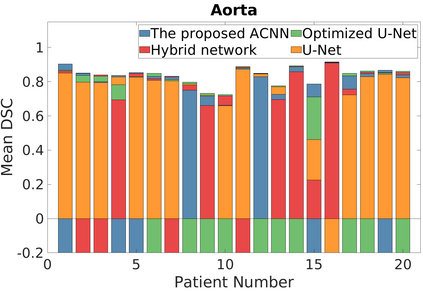

Deep Convolutional Neural Networks (DCNNs) are used extensively in biomedical image segmentation. However, current DCNNs usually use down sampling layers for increasing the receptive field and gaining abstract semantic information. These down sampling layers decrease the spatial dimension of feature maps, which can be detrimental to semantic image segmentation. Atrous convolution is an alternative for the down sampling layer. It increases the receptive field whilst maintains the spatial dimension of feature maps. In this paper, a method for effective atrous rate setting is proposed to achieve the largest and fully-covered receptive field with a minimum number of atrous convolutional layers. Furthermore, different atrous blocks, shortcut connections and normalization methods are explored to select the optimal network structure setting. These lead to a new and full-scale DCNN - Atrous Convolutional Neural Network (ACNN), which incorporates cascaded atrous II-blocks, residual learning and Fine Group Normalization (FGN). Application results of the proposed ACNN to Magnetic Resonance Imaging (MRI) and Computed Tomography (CT) image segmentation demonstrate that the proposed ACNN can achieve comparable segmentation Dice Similarity Coefficients (DSCs) to U-Net, optimized U-Net and hybrid network, but with significantly reduced trainable parameters due to the use of full-scale feature maps and therefore computationally is much more efficient for both the training and inference.